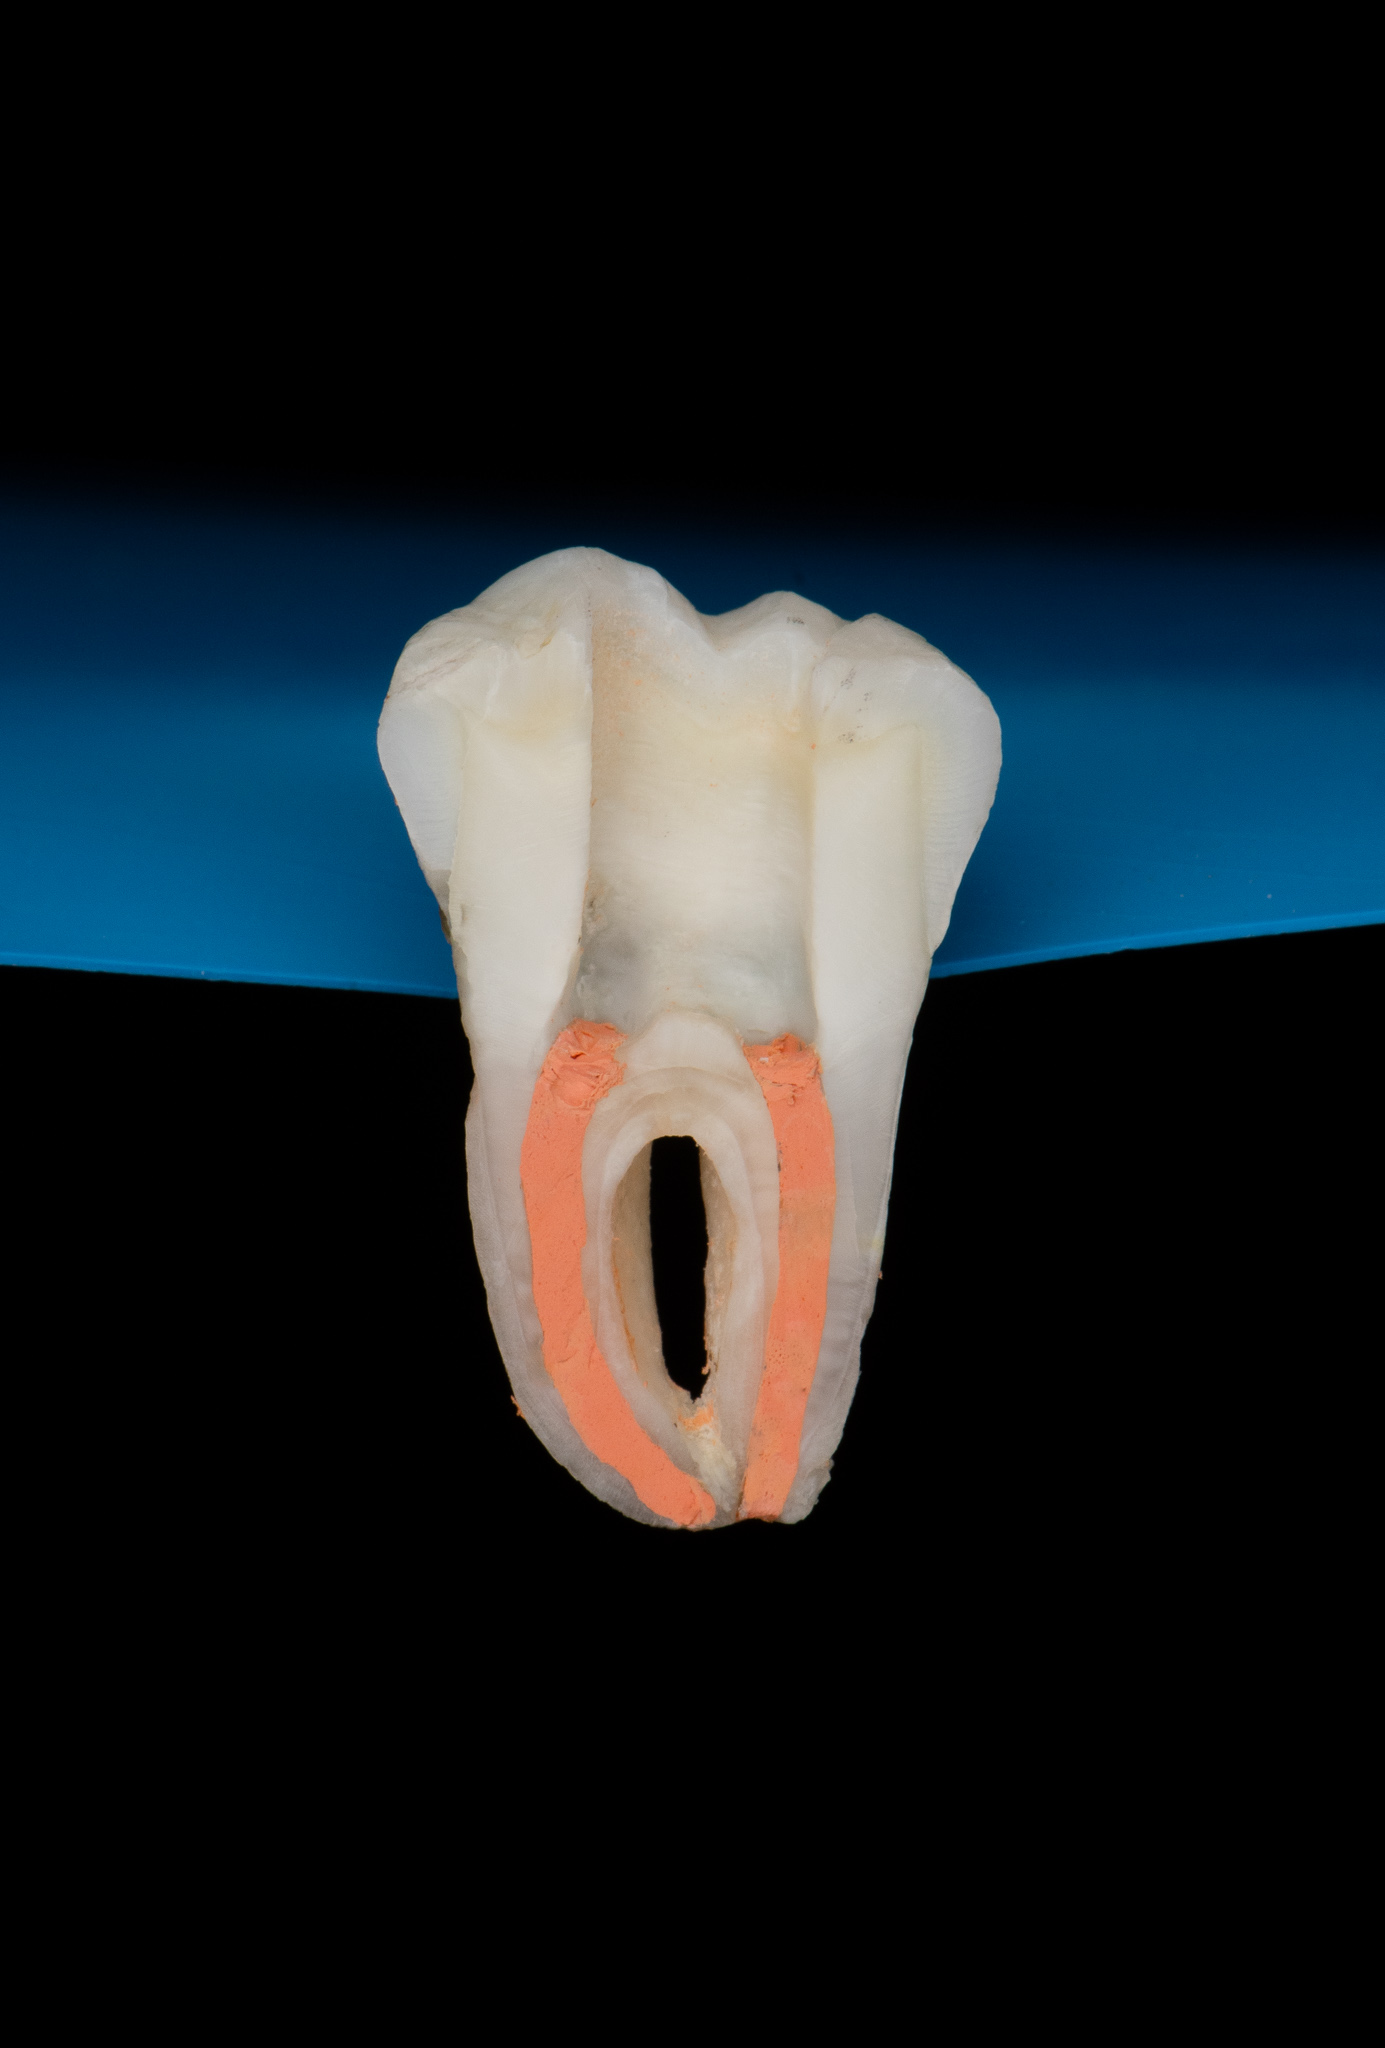

Endodoncja czyli leczenie kanałowe pozwala, na wiele lat, utrzymać w zdrowiu zęby martwe, które w przeciwnym razie wymagałby usunięcia. W naszym gabinecie prowadzimy leczenie kanałowe pierwotne jak również powtórne (ReEndo) z wykorzystaniem nowoczesnych technik i narzędzi takich jak mikroskop zabiegowy, rotacyjne systemy udrażniania kanałów czy wypełnienie płyną falą gutaperki.